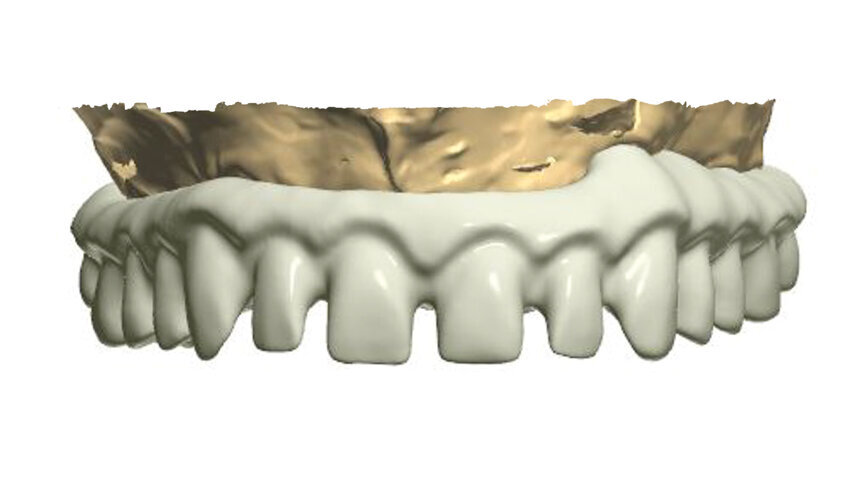

In order to prepare the bridge, a model was scanned and transferred onto a computer using software to design the bar (Fig. 1). The bar was designed by using special software in such a way that the whole design was transparent in the first phase so that the location of abutments and the position of the telescopic abutments at the frontal section could be visible (Fig. 2).

Having planned the proper shape and location of pillars for the porcelain crowns, the transparency was switched off (Fig. 3).

The next phase involved the planning of the size and shape of the final teeth, which, as porcelain crowns, will be glued onto the construction (Fig. 4). For that purpose, it is very helpful if on the design of the bar, a scan of the patient's temporary model prosthesis can be planted.

The patient must first approve the wax-up, in aesthetical and functional terms (Fig. 4). A computer programme for designing such constructions provides us with the possibility of viewing and designing the bar from all angles. Figures 5 to 9 show some exemplary prints of the views visible from the occlusal surface. Having finished the designing process, the bar should be visually inspected from the intragingival side (Fig. 10).